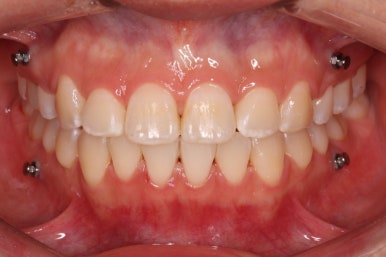

다시 이번 환자분으로 돌아가, 입 안모습을 보시겠습니다.

부산무턱교정 키다리아저씨치과에서 처음 내원하셨을 당시의 입 안의 모습입니다.

아래턱이 작아서 상대적으로 윗니들이 많이 돌출되었고, 뻐드러져 있습니다. 윗니들이 배열되어 있는 형태도 V자에 가깝게 입천장이 좁은 양상입니다.

중앙선도 잘 맞고 교합도 잘 마무리되었습니다.

중앙선, 교합, 뻐드러짐 모두 좋아졌고 이를 뽑고 교정했지만 발치 공간이 남지 않고 잘 마무리 되었습니다.